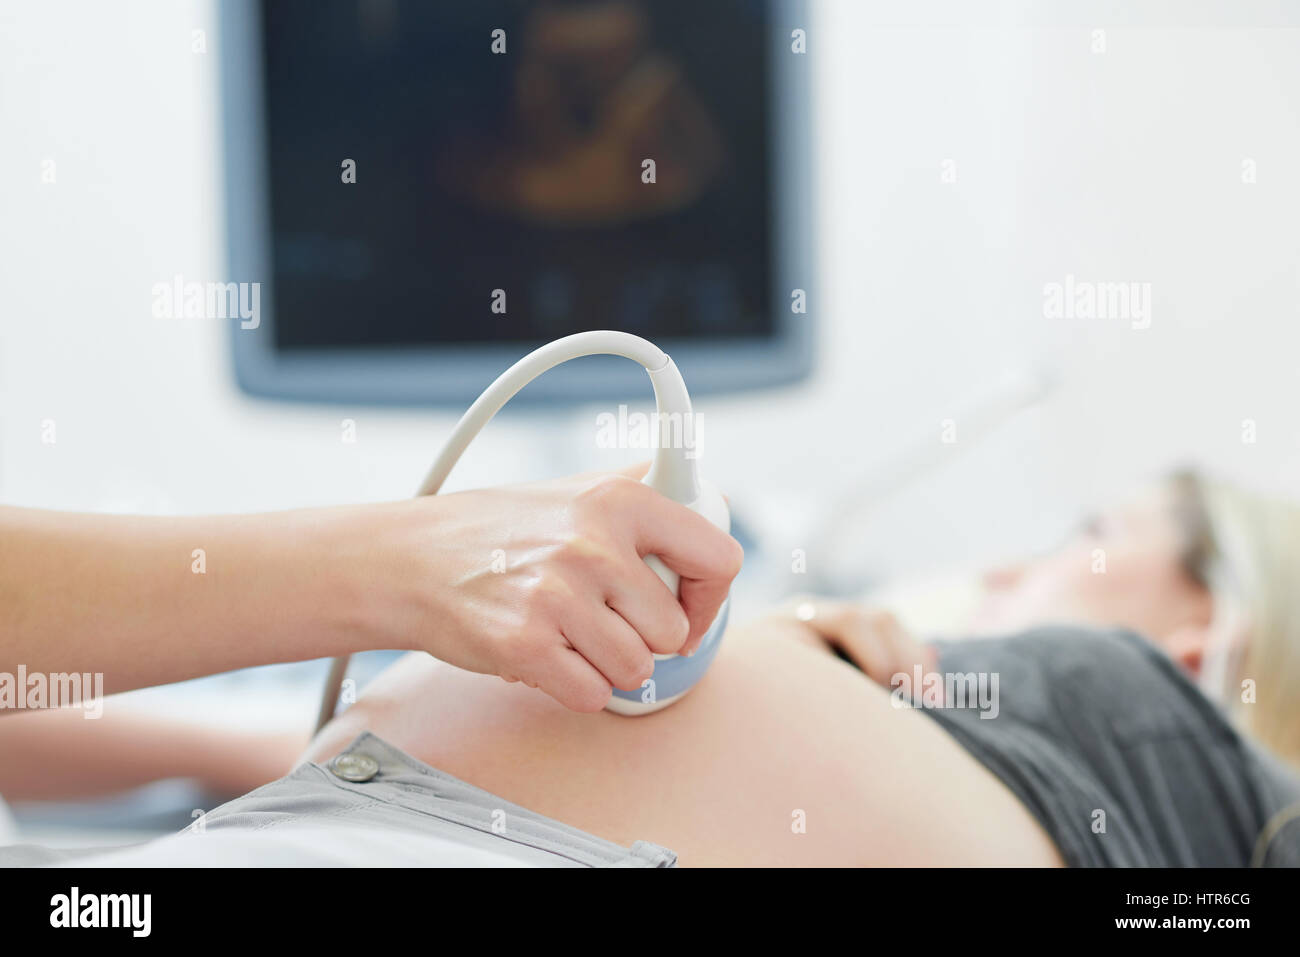

Medico utilizzando apparecchiature a ultrasuoni screening della donna incinta. Foto Stockhttps://www.alamy.it/image-license-details/?v=1https://www.alamy.it/foto-immagine-medico-utilizzando-apparecchiature-a-ultrasuoni-screening-della-donna-incinta-135734272.html

Medico utilizzando apparecchiature a ultrasuoni screening della donna incinta. Foto Stockhttps://www.alamy.it/image-license-details/?v=1https://www.alamy.it/foto-immagine-medico-utilizzando-apparecchiature-a-ultrasuoni-screening-della-donna-incinta-135734272.htmlRFHTR6CG–Medico utilizzando apparecchiature a ultrasuoni screening della donna incinta.